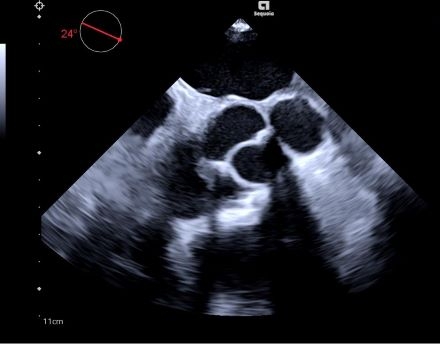

TEE done at a routine follow-up three years later revealed an echogenic sinus of Valsalva structure with a >1.2 cm wide neck communicating with the ascending aorta—findings consistent with pseudoaneurysm from pericardial patch dehiscence. Redo sternotomy and a modified Bentall procedure were performed, including explantation of the bioprosthesis, root and valve replacement with a bioprosthetic conduit, ascending aorta replacement, and coronary reimplantation. The procedure was successful with preserved cardiac function and clinical improvement.